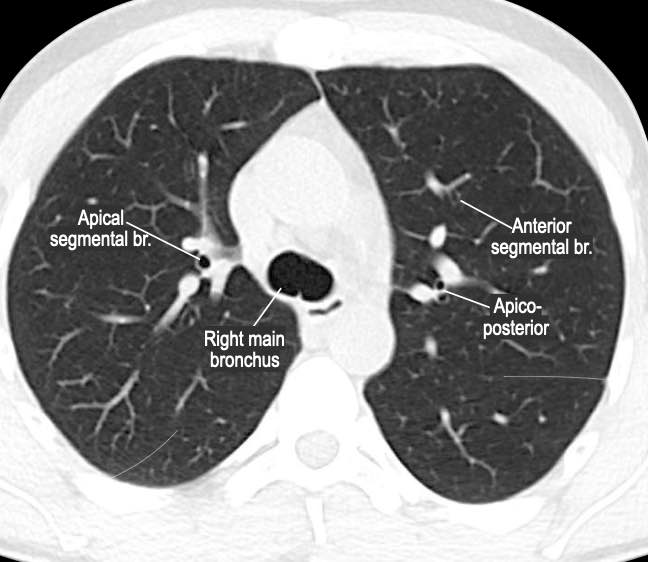

Phế quản trên CT

Cuộn qua các hình ảnh để quan sát khí quản phân chia thành phế quản chính phải và trái, sau đó tiếp tục phân chia thành các phế quản thùy và phế quản phân thùy.